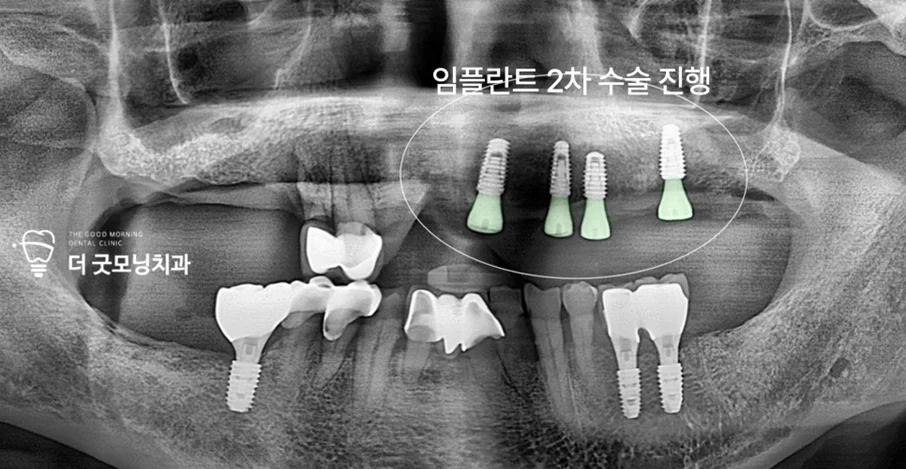

Step 5. 우측 발치 및 2차 수술

브릿지 지대치로 사용하던 우측 사랑니와 소구치에 통증이 발생하여 먼저 발치를 진행했습니다. 치유 기간 이후 힐링 어버트먼트를 체결하는 2차 수술을 완료했습니다.